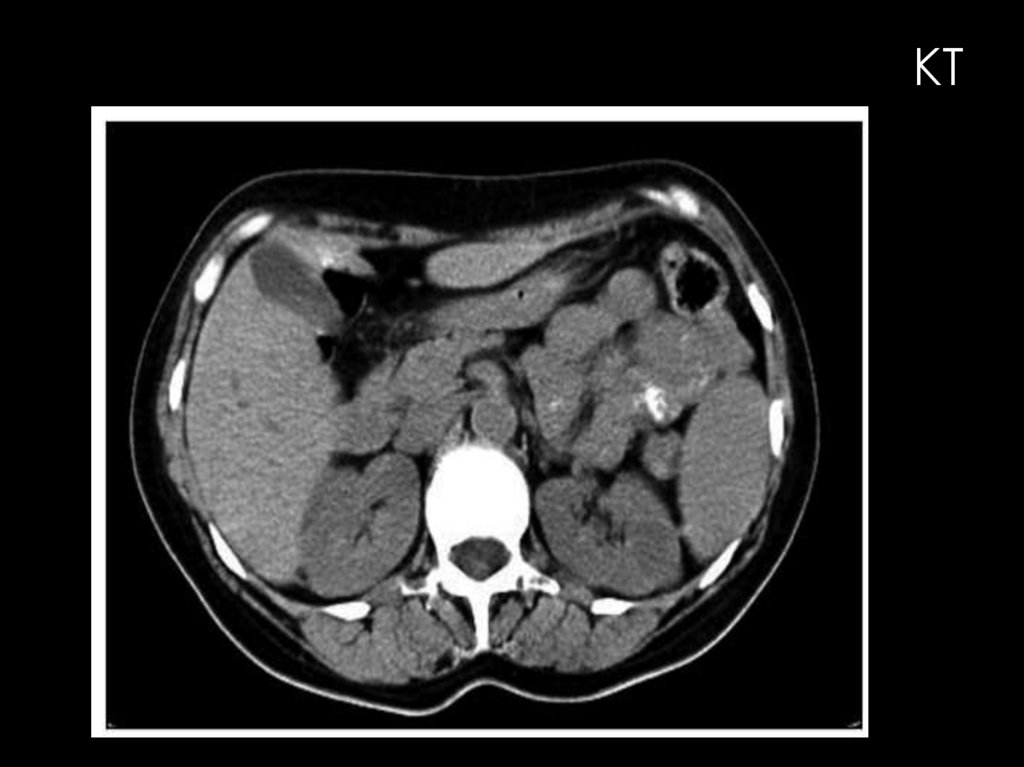

КТ

РЕНТГЕНОВСКАЯ КОМПЬЮТЕРНАЯ

ТОМОГРАФИЯ

КТ в урологической практике широко используется главным

образом для исследования почек

КТ-изображение почек в норме всегда отчетливое даже при

нативном исследовании, что обусловлено большой разницей

рентгеновской плотности самих почек (+30... +40 HU) и окружающей

их жировой клетчатки (-70... - 130 HU). Разница плотностей

обеспечивает также дифференцирование изображения почек на

паренхиму и почечный синус, тоже содержащий жировую клетчатку